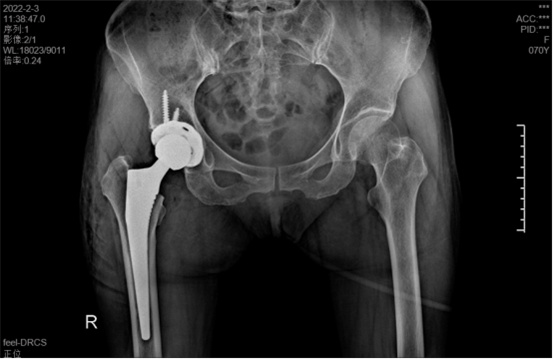

據(jù)羅軍主任介紹,他們首先將鄭阿姨的術(shù)前CT數(shù)據(jù)導(dǎo)入到系統(tǒng)中,通過自動(dòng)識別骨盆和股骨建立了計(jì)算機(jī)數(shù)字三維模型。AI HIP顯示患者適合使用合適的髖臼杯、股骨柄、標(biāo)準(zhǔn)陶瓷球頭、陶瓷內(nèi)襯,并精準(zhǔn)定位了截骨線,有效幫助醫(yī)生在手術(shù)中做到精確截骨。

在完善相關(guān)檢查充分評估患者身體情況及手術(shù)風(fēng)險(xiǎn)后,羅軍主任改變傳統(tǒng)手術(shù)方式,在易觀俊主治醫(yī)師、柴重喜醫(yī)師等助手的配合下,為鄭阿姨實(shí)施了人工智能規(guī)劃輔助DAA入路全髖關(guān)節(jié)置換術(shù)。

術(shù)中假體植入和術(shù)前規(guī)劃完全一致

術(shù)中,醫(yī)生在患者髂前上棘外側(cè)切開約8cm長的切口,小心翼翼地利用闊筋膜張肌與縫匠肌之間的間隙露出髖關(guān)節(jié)。經(jīng)過一番精細(xì)、高難度的操作,成功植入人工髖關(guān)節(jié)組件,以取代受損的股骨頭和髖臼。由于手術(shù)切口小,肌肉組織未受損,鄭阿姨恢復(fù)很快,術(shù)后第1天就能下床活動(dòng)。